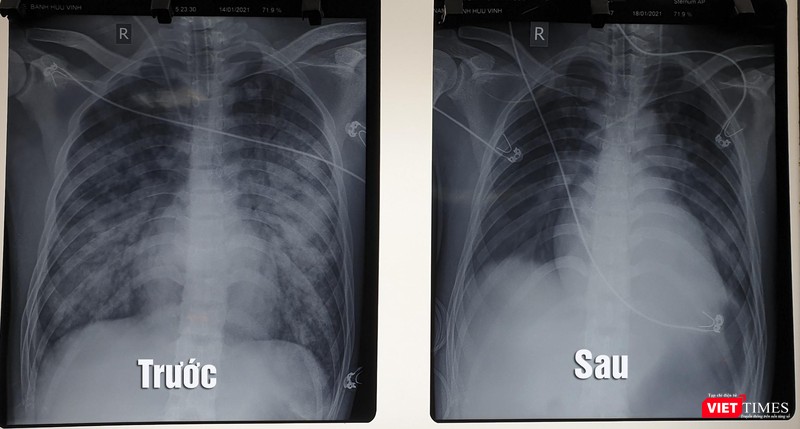

Toàn viện đã hội chẩn tối khẩn với nhiều chuyên khoa, để quyết định can thiệp bằng ECMO, do bệnh nhân vừa sốc tim kết hợp suy hô hấp nặng, phim chụp X quang phổi thâm nhiễm lan tỏa hai phế trường nên kíp hội chẩn hội ý dùng phương pháp can thiệp song song vừa hỗ trợ tim và hỗ trợ phổi nhân tạo cùng lúc (phương pháp VAV ECMO), kết hợp với các phương pháp điều trị hỗ trợ tích cực khác như thở máy, lọc máu liên tục, lọc thận cấp cứu và hồi sức tim mạch nâng cao.

Hình ảnh X quang phổi của bệnh nhân trước và sau khi điều trị bằng kỹ thuật ECMO (Ảnh: BVCC) |